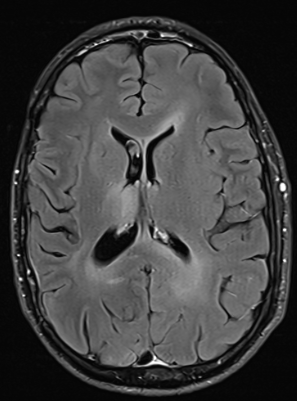

FET-PET confirms it

1748327448172.png

One month later (patient did not undergo tratment yet), MRI finding becomes clearer

1748327624012.png